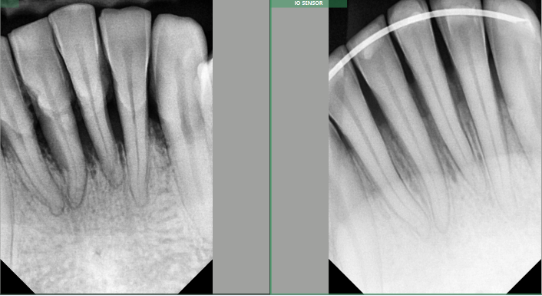

This technique is minimally invasive with faster recovery. Don't take my word for it. Look at the following pictures, and remember, there is no bone graft done; this is the patient's own body healing and creating one. Let's see one of my patient's cases.

A 30-year-old male comes to the Office with severe gum disease. His lower teeth were moving, and the X-rays showed severe bone loss; the usual proposed treatment is extraction and replacement with partial dentures. The teeth were so mobile that an ortho retainer was needed(as a cast) post-LANAP protocol to give a chance to the newly formed bonnet to break with the mobility when chewing.

We did LANAP a year ago, and this is the X-ray of the same lower front teeth on February 13, 20025. Look at the photo after; there has been true bone regeneration. HE NO LONGER NEEDS EXTRACTION OR DENTURES!!!!